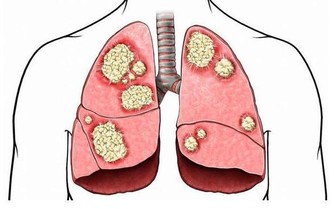

中醫理論上認為,針灸、按摩極泉穴都有著寬胸寧神的效果。除此之外,經常搓洗腋窩,還能治療肋間神經痛等神經系統方面的疾病,包括肩周炎等。而且腋窩處還有很多動靜脈血管,並且有大量的淋巴組織,擔負著血液輸送的重要使命,而且還有免疫防禦功能。經常搓洗腋窩,可以有效的改善身體的血液供應,並且刺激淋巴,改善心肺功能,增強食慾,並且還能提高消化能力。